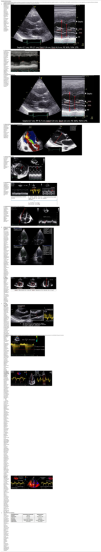

La ecocardiografía Doppler (ED), en especial la ETE, inicialmente nos proporcionará la información necesaria en la toma de decisión (necesidad de un dispositivo, y tipo o tipos de dispositivos a implantar), así como en la identificación de patología que contraindique o dificulte el implante (patología valvular aórtica, presencia de foramen oval permeable, trombosis, disección, patología vascular arterial, miocardiopatía hipertrófica, etc.).

Una vez decidido el tipo de dispositivo a implantar, será de gran ayuda en el proceso de inserción, de posicionamiento exacto de cánulas, de detección de complicaciones, de evaluación de la eficacia del dispositivo implantado y en el destete.

Balón de contrapulsación intraaórtica (BIAC) (fig. 5)- •

Comprobar la presencia de la guía en la aorta descendente y asegurar que la sonda esté a 2-5cm de la arteria subclavia izquierda. Si no es posible visualizar la subclavia, se puede tomar como referencia el borde inferior del arco aórtico.

Es importante visualizar las guías durante todo el proceso. Las vistas transesofágicas bicaval y bicaval modificada proporcionan una adecuada visualización de la vena cava inferior, de la vena cava superior, de la válvula tricúspide y de la aurícula derecha38.

La posición apropiada de la cánula puede determinarse por ETT o ETE cuando se requiera (Video 5 en material suplementario).

Permite determinar la causa de flujos inadecuados, que son frecuentes durante el soporte con ECMO.

La ETE puede usarse para visualizar la guía para la cánula de retorno en la aorta abdominal superior y evitar una mala posición de la cánula en alguna rama vascular39. La ubicación óptima de la cánula de drenaje venoso a través de la vena femoral es en la aurícula derecha.

Es esencial la monitorización ETT/ETE del diámetro de cavidades para asegurar un adecuado vaciamiento de los ventrículos, así como de la apertura de la válvula aórtica. El aumento de la poscarga propiciado por el ECMO-VA periférico junto con la disfunción VI severa puede propiciar el cierre de la válvula aórtica y se podría generar la coagulación de cavidades intracardiacas.

La monitorización de la función biventricular permite una detección temprana de mejora, que deberá evaluarse modulando los flujos de ECMO. Si hay recuperación, la contractilidad ventricular estará aumentada, o se mantendrá sin dilatación del VD y sin deterioro del volumen latido evaluado por integral tiempo velocidad (ITV) a nivel del TSVI.

La ecografía tiene un papel importante en la evaluación previa, durante el implante y en el seguimiento posterior.

Tras el implante de la asistencia, la ETT/ETE permite la valoración de:

Función ventricular derecha. Fracaso de VD tras asistencia izquierda, que aparece hasta en el 20-25% de casos y necesitará, en el 10-15%, implantar asistencia derecha.

Mal funcionamiento por trombosis en el dispositivo. En caso de trombosis evidente con ETT es suficiente, pero en pocas ocasiones hay evidencia directa de la formación del trombo. La sospecha debe plantearse en caso de dilatación del VI, incremento de la insuficiencia mitral y la frecuencia de apertura de la válvula aórtica.

En un dispositivo de asistencia ventricular con funcionamiento normal, al incrementar las revoluciones por minuto en su flujo, el diámetro ventricular izquierdo, la apertura valvular aórtica y la insuficiencia mitral disminuyen, mientras que el tiempo de desaceleración transmitral se incrementa. Cuando ocurre lo contrario, se debe sospechar trombosis del dispositivo.

Mal funcionamiento por succión. Cualquier situación que disminuya la precarga puede ocasionar efecto de succión. El dispositivo de asistencia ventricular genera una descompresión en el VI dilatado, generando una succión negativa en la cánula de entrada en el ápex cardíaco, que puede causar un movimiento septal hacia la izquierda. Una reducción en la precarga puede conllevar un bajo llenado del ventrículo asistido, aproximándose estructuras cardiacas normales a la cánula posicionada en el ápex cardiaco y pudiendo causar obstrucción de la cánula por succión de estructuras cardiacas adyacentes (trabéculas, músculo papilar, septo), con caída del GC y aparición de arritmias40.

Destete. La valoración de la recuperación miocárdica se basa en criterios hemodinámicos y ecocardiográficos (FEVI >40-45% con un diámetro telediastólico <45-60mm).

Evaluación del posicionamiento correcto del catéter Impella: debe realizarse siempre que se activen alarmas de posición, se observen flujos inferiores a los esperados o signos de hemólisis (tabla 4).

Tabla 4.Evaluación del posicionamiento del catéter Impella

• Área de entrada del catéter 3,5 cm por debajo del anillo de la válvula aórtica• Zona de salida del catéter muy por encima de la válvula aórtica• Catéter en ángulo hacia el vértice del VI lejos de la pared del corazón y sin enrollarse ni bloquear la válvula mitral• Patrón de mosaico por Doppler color denso de turbulencia por encima de la válvula aórtica cerca del área de salida del catéter - •